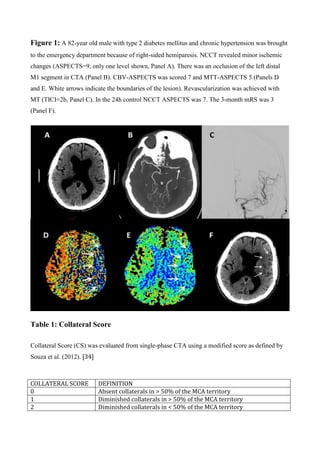

Figure 1. Occlusion of the right M1 segment of the MCA. Adapted from

http://www.strokecenter.org/patients/about-stroke/ischemic-stroke/